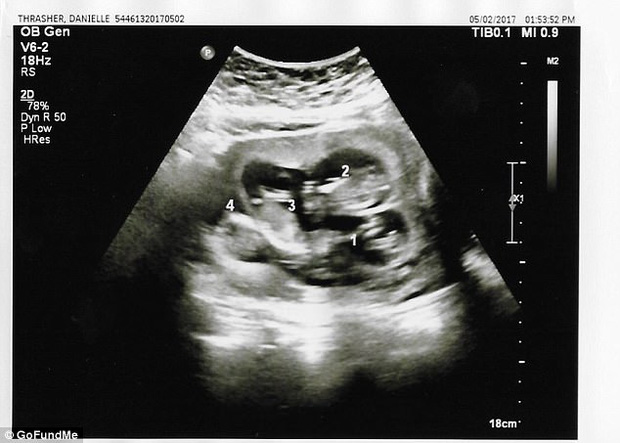

Phải tới lần siêu âm thứ 3 thì các bác sĩ mới phát hiện ra em bé thứ tư nằm trong bụng Danielle.

Thế nhưng, mọi thứ cứ như muốn "trêu ngươi" cặp tình nhân trẻ khi đến tuần thai thứ 13, trong một lần siêu âm, chị nhận được kết luận của bác sĩ rằng trong bụng chị đang có tới 4 bào thai đang phát triển.

Tuy nhiên có một điều cả hai vô cùng thắc mắc đó là tại sao đến tận lần siêu âm thứ 3 các bác sĩ mới phát hiện ra em bé thứ tư trong bụng Danielle.

Trả lời về vấn đề này, các bác sĩ làm việc trực tiếp với Danielle giải thích: "Bào thai thứ tư bị che khuất bởi lỗ rốn của Danielle, điều đó khiến chúng tôi không thể nhìn thấy trong những lần siêu âm trước. Còn việc mọi người hỏi rằng tại sao không kiểm tra kĩ trong quá trình siêu âm thì chúng tôi cho rằng việc thai phụ có 3, 4 hay 5 con không nằm trong dự đoán của chúng tôi và chúng tôi không có bất cứ lý do nào để kiểm tra xem liệu thai phụ đang mang bao nhiêu thai, nhất lại là trong những trường hợp như thế này, vị trí nằm của đứa trẻ không khiến chúng tôi đặt bất cứ nghi vấn nào".

Nói thêm về trường hợp của chị Danielle, các bác sĩ cho biết, 4 bào thai trong bụng được tạo thành từ 4 trứng và 4 tinh trùng riêng biệt. Đây là một điều khá hiếm khi xảy ra. Trong 700.000 ca mang thai tự nhiên thì chỉ có 1 ca tương tự như vậy.